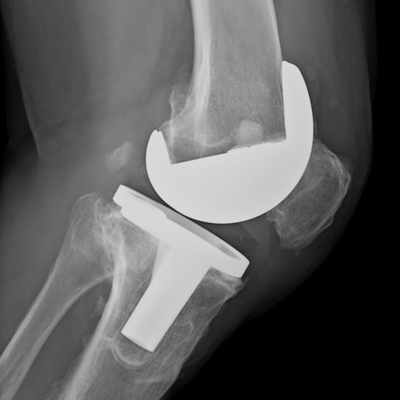

Eklem Protez Cerrahisi

Hareketliliğini kaybetmiş, hastaya ağrı veren kalça, diz ve omuz eklemi protez cerrahisiyle hareketliliğini yeniden kazanabilir.